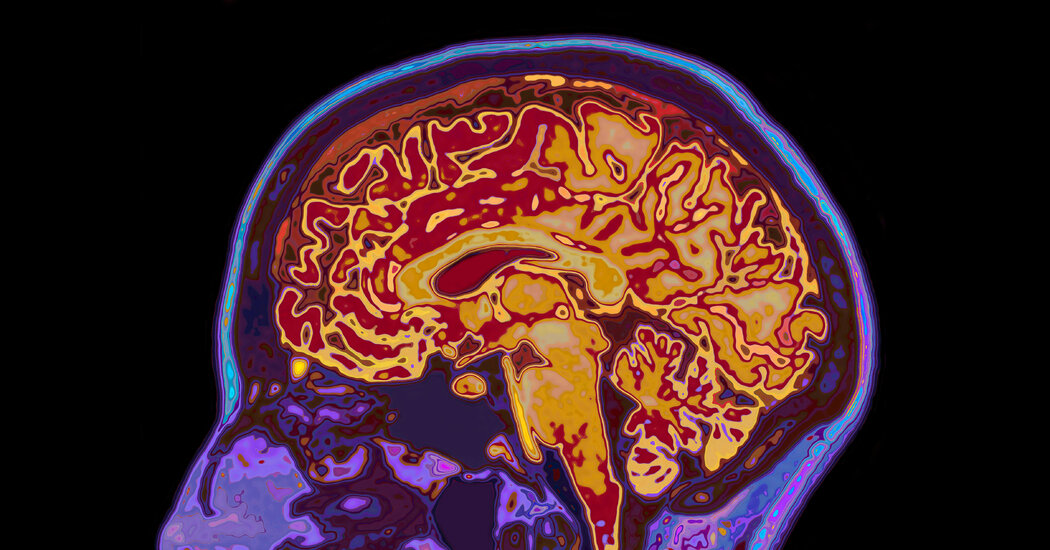

A study from the Singapore University of Technology and Design suggests that early bilingualism leads to beneficial structural changes in the brain, including increased gray matter volume and cortical thickness, which contribute to a stronger cognitive reserve. This reserve is crucial for maintaining social cognitive abilities into older age, highlighting bilingualism’s potential to enhance mental flexibility and attention control. The findings emphasize the importance of bilingualism for healthier aging and encourage early language learning to preserve cognitive function and social cognition in later life.